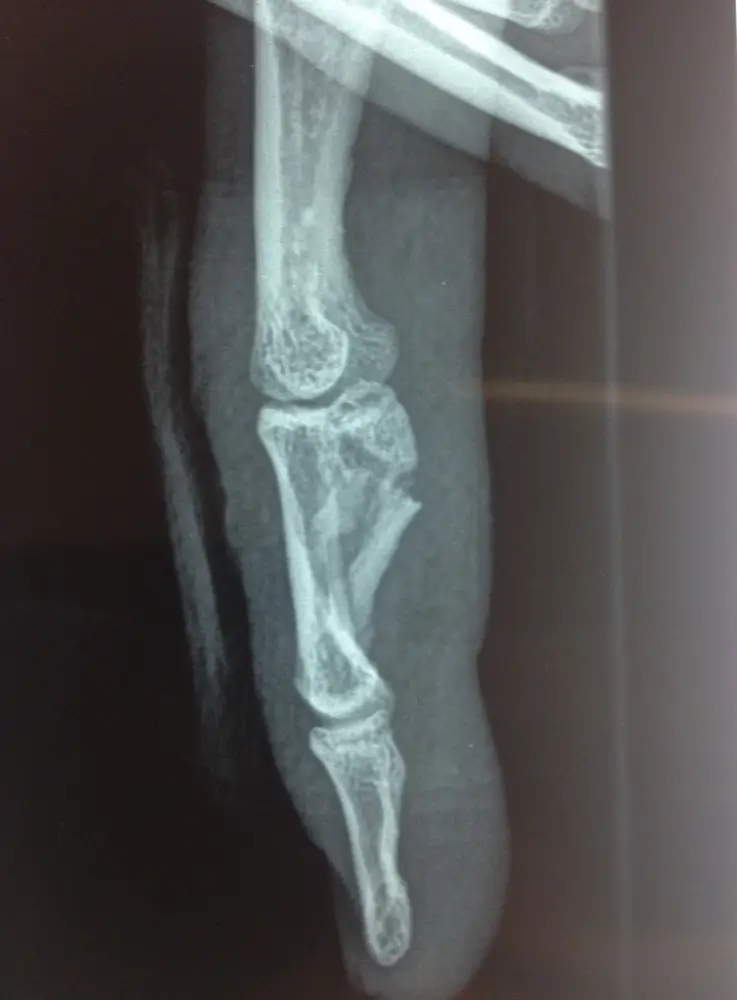

- fractures